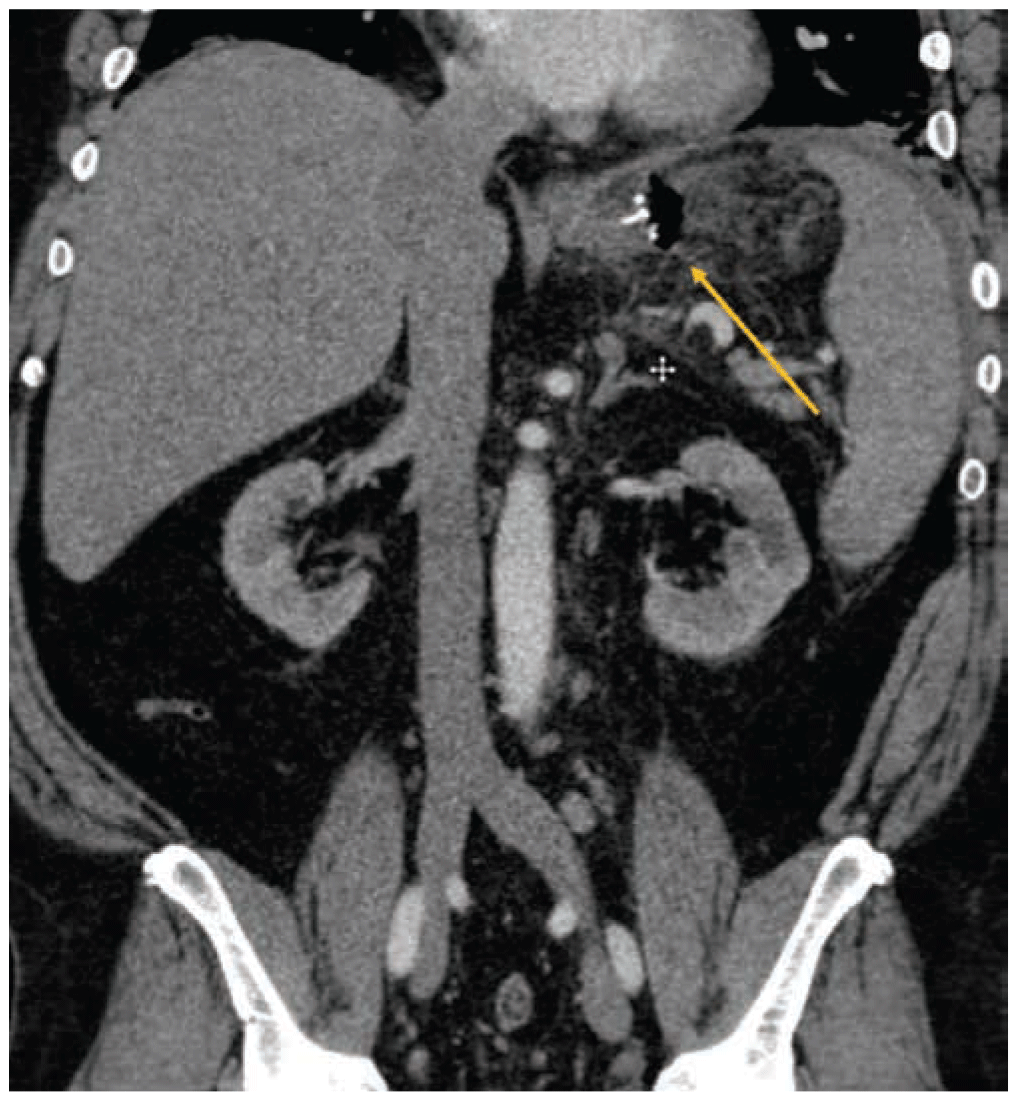

Advanced and Recurrent Rectal Cancer

- Patients with colorectal cancer, due to increased age and exposure to neoadjuvant therapy, are likely to have or obtain functional deficits prior to surgery. Optimizing patients is crucial for minimizing postoperative complications after radical resections. It has been established that patients with poor physical fitness experience a greater number of complications after surgery, are at greater risk for death, and have a significant delay in regaining their baseline functional status. Prehabilitation is an increasingly studied novel approach to patient optimization through a process of increasing functional capacity prior to colorectal surgery. Several small studies have shown beneficial functional outcomes, although the clinical impact, as far as decreased morbidity and mortality, has not been clearly demonstrated.

- With an aggressive multidisciplinary approach, the overall 5-year survival rate of LRRC is 25 to 67%. The quality of the surgery has a large impact on patient survival; therefore, an aggressive surgical strategy to gain a negative resection margin is vital to patient outcomes